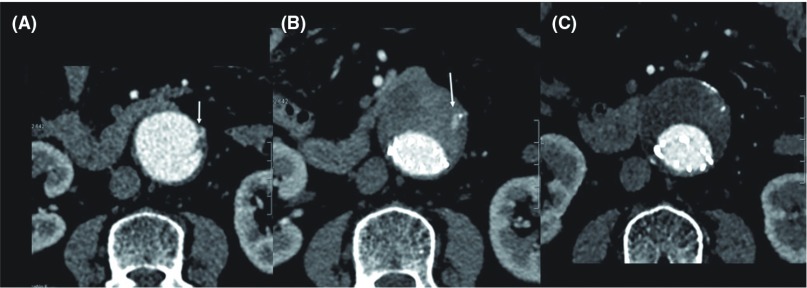

Patients were divided into three follow-up groups based on the CT findings. Group N (106 patients; 89%): no type II endoleak from the IMA; Group T (10 patients; 8.3%): transient type II endoleak from the IMA; Group P (4 patients; 3.3%): persistent type II endoleak from the IMA with or without secondary intervention. When the type II endoleak spontaneously disappeared during the follow-up period, it was defined as transient (Fig. 1).

Fig. 1.

A 74-year-old woman underwent EVAR with Powerlink for treatment of AAA, 46 mm in diameter (A). Stenosis of the orifice of the IMA was caused by mural thrombus and calcification (arrow). Computed tomography (CT) 1 week after EVAR showed type II endoleak from the IMA (B, arrow). However, CT 24 months after EVAR showed spontaneous disappearance of type II endoleak (C). AAA: abdominal aortic aneurysm; IMA: inferior mesenteric artery; EVAR: endovascular aortic aneurysm repair.